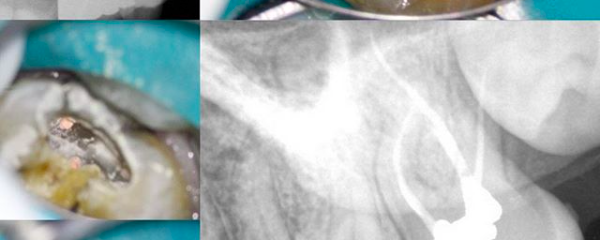

#2.6 NP/SAP, 2 visits, asymptomatic at 2nd visit, System B gingivectomy. Tried to apply best practices in endodontics including: finding all canals, preserving coronal and radicular dentin, immediate coronal restoration with adequate marginal adaptation with no voids and finally, proper documentation. Far from perfect, but it starts with making the right decisions and then getting […]